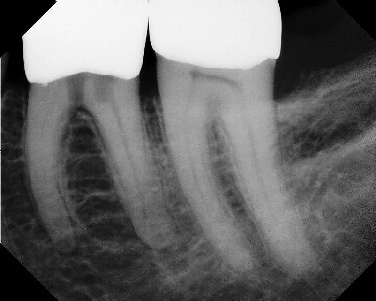

COMPLICATED ANATOMY LARGE LESIONS CALCIFIED CANALS PERFORATION / RESORPTION SEPARATED INSTRUMENTS SURGICAL CASES RETREATMENT / pOST REMOVAL OPEN APICES ACCESS THRU CROWNS Root Canal Case Portfolio